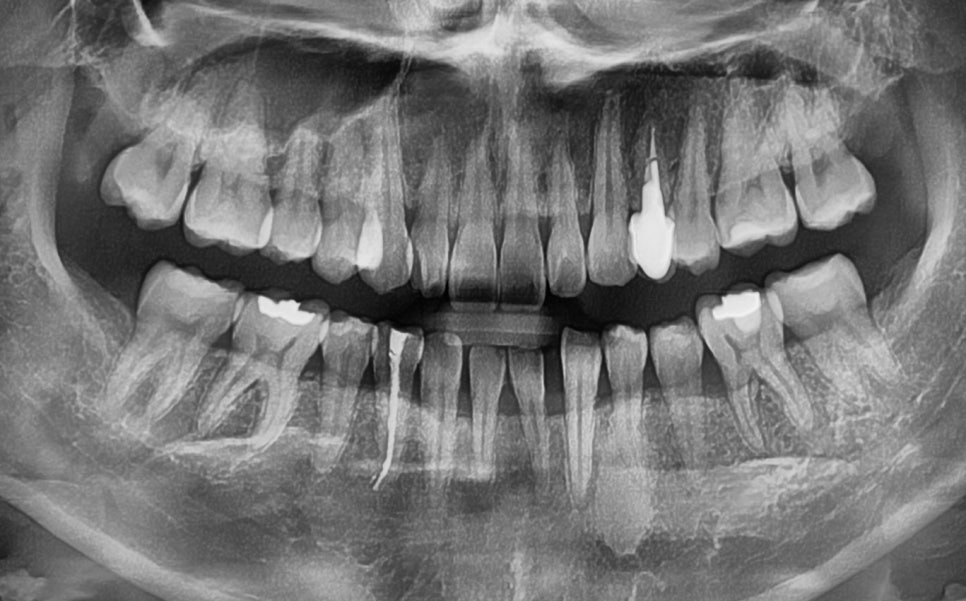

| 2. 정밀한 초진 검사가 성공의 첫걸음

23.10.20

먼저 구강 내 전체 상황을

파악하는 것부터 시작합니다.

위 사진을 보면

전체적으로 치열이 틀어져 있는 것을

확인할 수 잇었으며

결손된 부위로 인해

아랫니가 벌어져 있는 것을

확인할 수 있습니다.